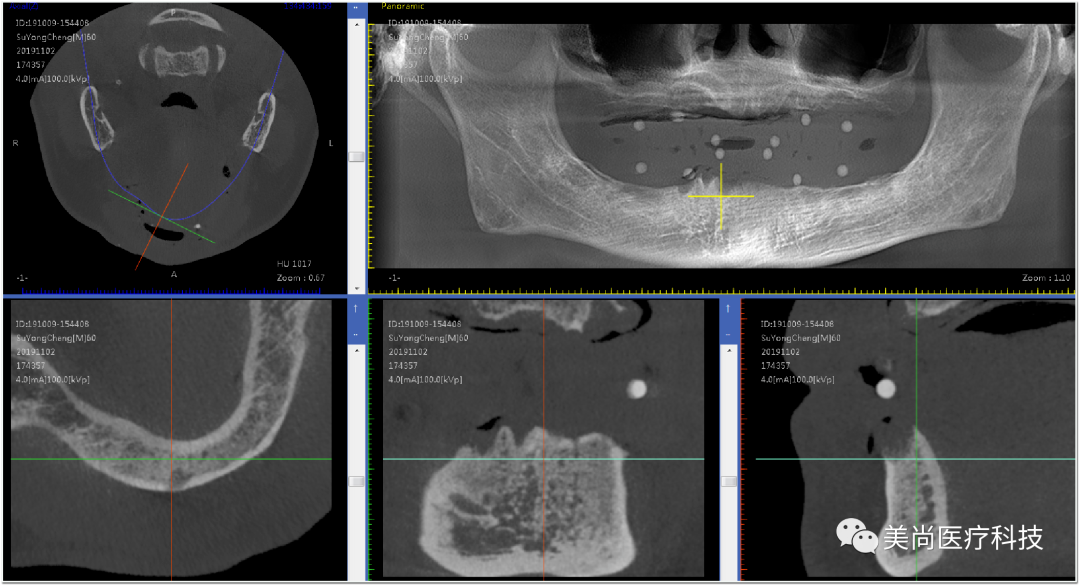

制作种植导板